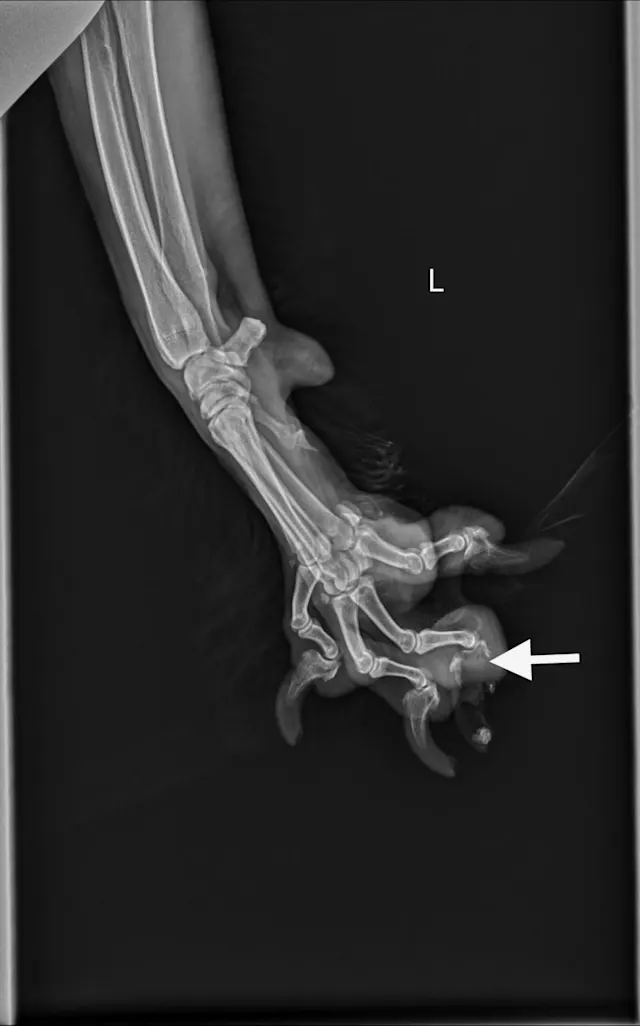

Digit melanoma

A single craniocaudal radiograph illustrates the forepaws of a 12-year-old neutered male Airedale terrier with digit melanoma. Moderate circumferential soft tissue swelling of the 5th digit of the left thoracic limb and significant lysis of the distal phalanx can be noted (arrows). The aggressive monostotic lesion of the distal phalanx of the 5th digit and associated soft tissue swelling are consistent with digital melanoma, which was confirmed via histopathology after digit amputation.